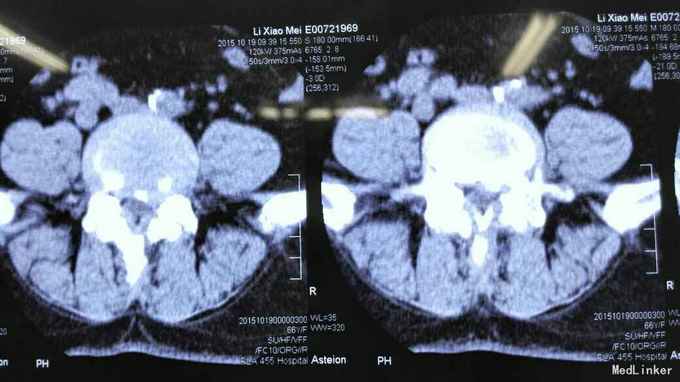

查体符合腰5神经根受压体征。腰椎CT、MRI提示腰4/5椎间盘突出,椎管狭窄。

考虑腰椎间盘突出伴椎管狭窄症。行椎间孔镜下髓核摘除,椎间孔成形。